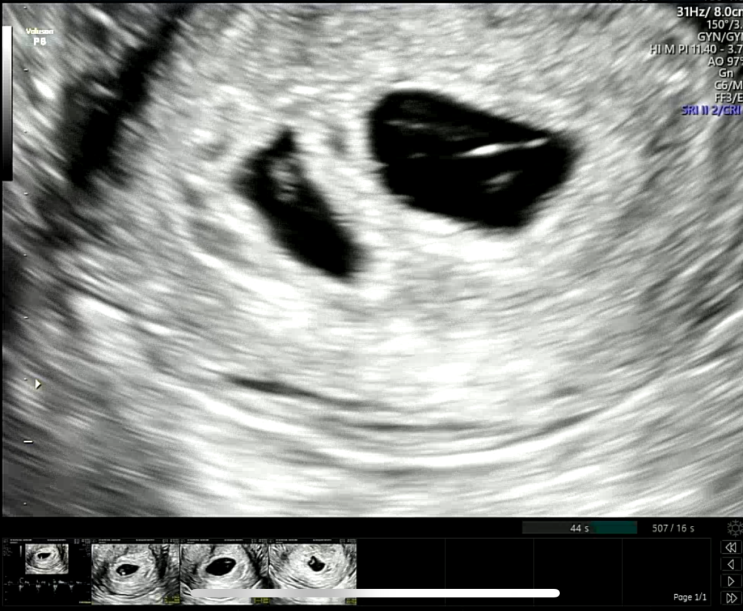

만 35세 노산임신 배니싱트윈 니프티검사 결과 / 분당제일여성병원

배니싱트윈 (쌍둥이도태 ) 확정후 방문한 15주차 분당제일여성병원 한성식 박사님 대기가 길어서 우선 니프...